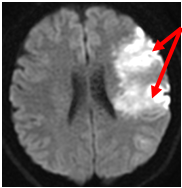

MRI;拡散強調画像

【MRI;拡散強調画像】

MRI;FLAIRA

【MRI;FLAIR】

MRIでは1.5cm以下の小さな梗塞として描出。